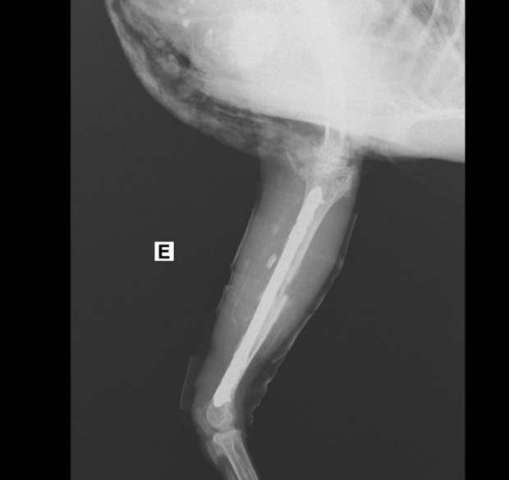

شهدت مدينة مرسى علم واقعة تعد الأولى من نوعها حيث تم إجراء عملية جراحية لإنقاذ  " دجاجة " بعد سقوطها من سطح  أحد المنازل  وإصابتها بكسور فى قدميها وإصرار صاحبها السويسرى الجنسية على علاجها حتى لو تطلب الأمر سفرها لخارج مصروقد إستغرقت الجراحة التى أجراها الطبيبان البيطريان محمد أحمد وإيمان أبوالمجد بإحدى العيادات بمدينة سفاجا  وتم خلالها تركيب شريحتين و6 مسامير بتكلفة 7 آلاف جنيه.

وكان قد إستقبلت عيادة الطبيبين الدجاجة فى  حالة إعياء شديدة وغير قادرة على الحركة وطلب صاحبها السويسرى الذى يعيش فى مصر إجراء الإسعافات اللازمة لها مهما تكلفت من أموال وإذا لم يكن هناك أمل فى علاجها تموت بالقتل الرحيم بعد تخديرها وقد تم إجراء بعض التحاليل الطبية للتأكد من سلامة أعضاءها الحيوية  والتواصل مع أطباء خارج مصر وتم إتباع الخطوات الطبية و تخديرها كلي بالاستنشاق وتظل بالعيادة لمدة يومين للملاحظة

وتضع "ليسكي"، قدميها في الجبس لمدة شهرين وأثناء هذه الفترة تقوم بعمل جلسات علاج طبيعي تتراوح بين شهرين و3 أشهر حتى تستطيع المشي بدون تعرضها لإعاقة حركية بالإضافة لكورس علاج مضاد حيوي ومسكن ومضاد إلتهاب وتجلس على كرسي متحرك لحين فك الجبس، حتى يمكنها التحرك بحرية.